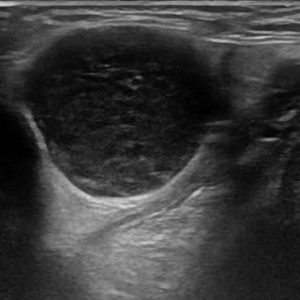

U tuyến nước bọt

Lượt xem: 138» 19-01-2021 -

U tuyến nước bọt

Lượt xem: 153» 19-01-2021 -